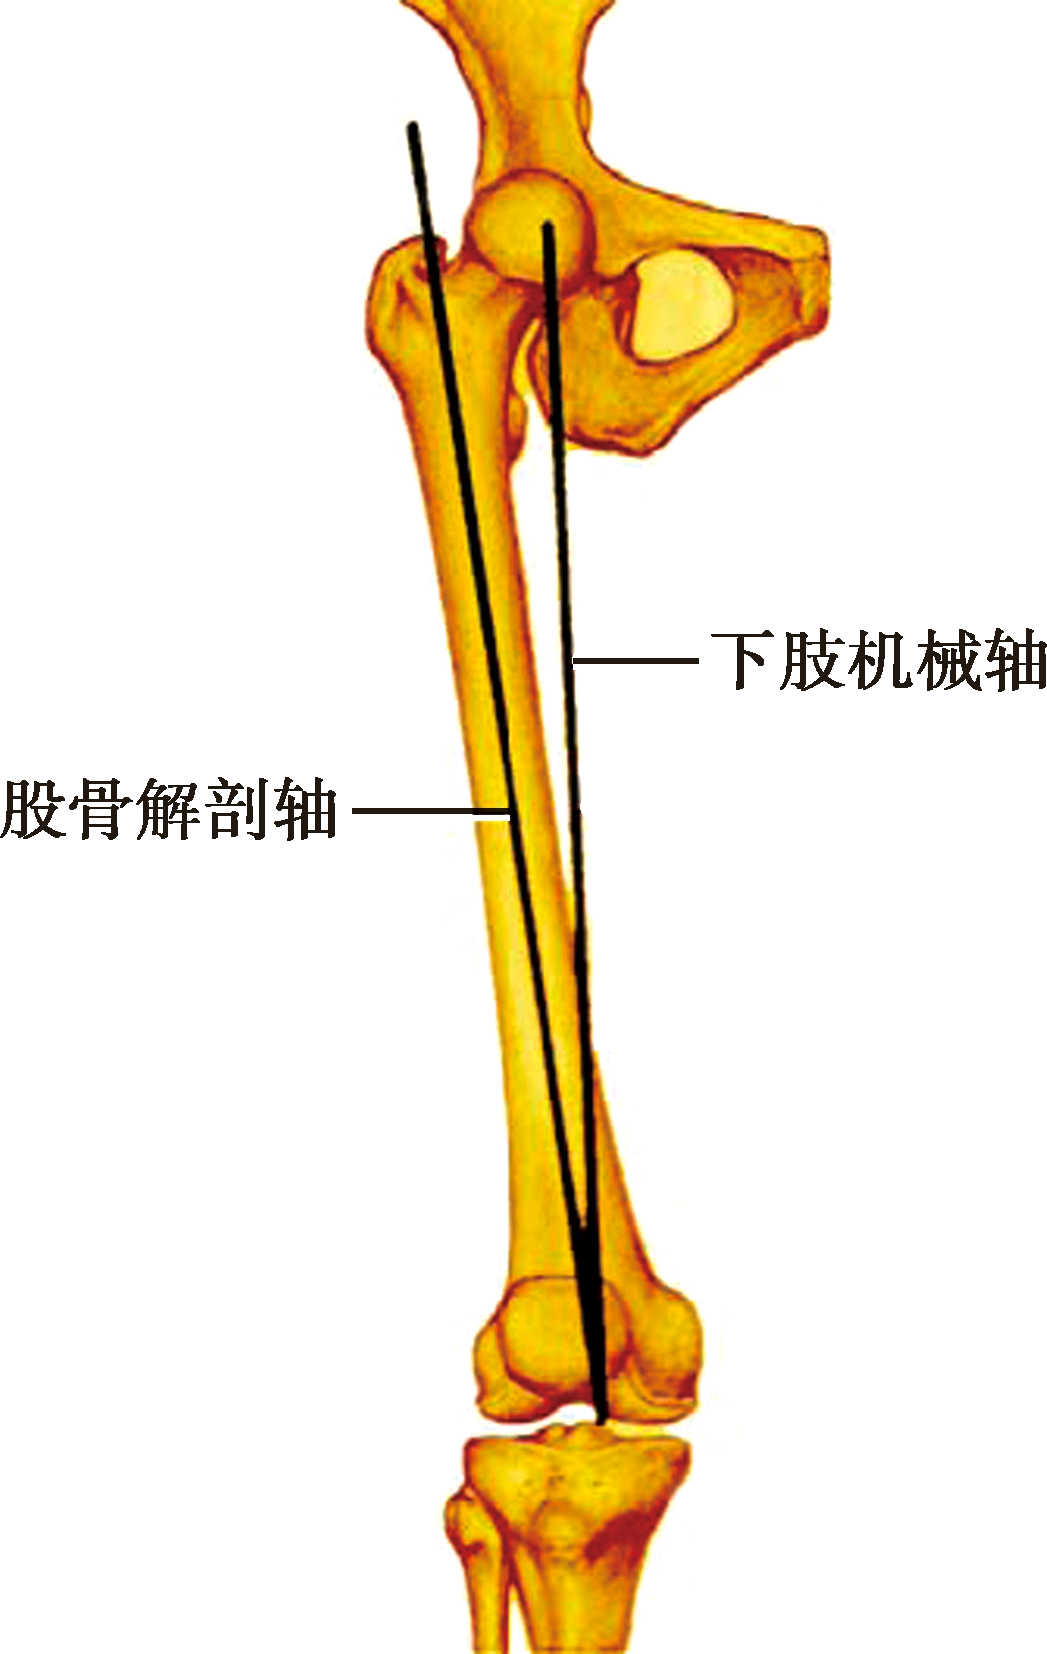

股骨解剖轴:股骨大转子尖与股骨髁间窝中点的连线

股骨解剖轴是股骨大转子尖与股骨髁间窝中点的连线。股骨解剖轴纵贯股骨髓腔中心。股骨解剖轴与机械轴的夹角平均约6°,临床上称其为“远端股骨角”。